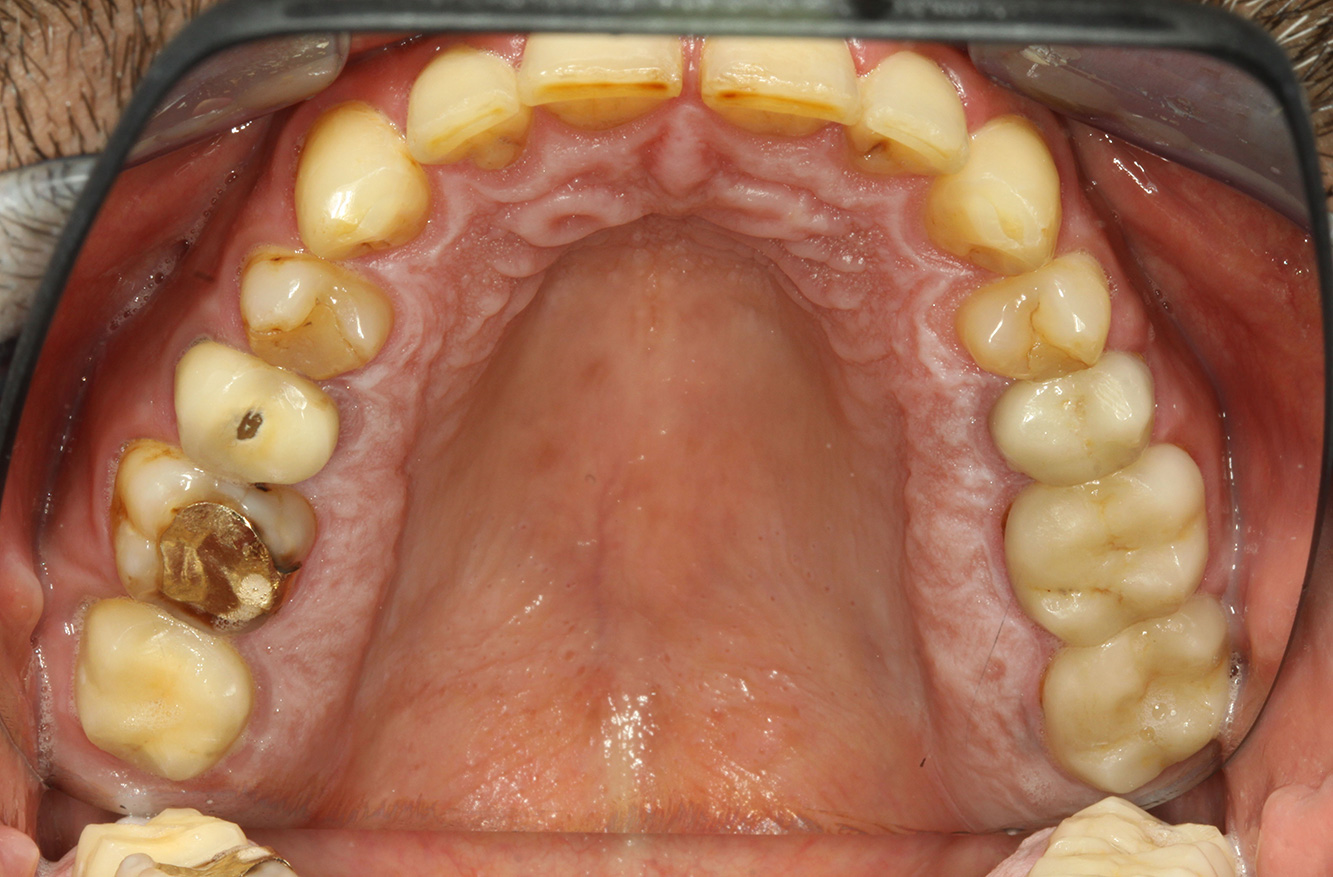

Der Endokarditis-Patient mit aktiven Kariesläsionen*

Der Patient ist 39 Jahre mit Z.n. Herzklappenersatz wegen Klappenfehlers und Endokarditis. Als Antikoagulans (Gerinnungshemmer) wird regelmäßig ASS 100 eingenommen. Aus dem Bereich Lebensstil ist die Ernährungsweise als kariesfördernd einzustufen, da mit hoher Regelmäßigkeit zuckerhaltige Lebensmittel sowie sechs bis sieben Mahlzeiten täglich verzehrt werden. Die Mundgesundheit des Patienten zeigt ein mittleres Kariesrisiko mit aktiven Läsionen. Das Parodontitisrisiko ist niedrig, es besteht eine Gingivitis. Es ergeben sich folgende Empfehlungen für die Prophylaxebehandlung.

Zur weiteren Unterstützung der Kariesprävention ist eine Fluoridierung, besonders um der Neuentstehung im Bereich der Restaurationsränder vorzubeugen, und eine Versiegelung der Wurzeloberflächen empfehlenswert. Beide Maßnahmen können die angegebene Temperatursensibilität der Zähne reduzieren.